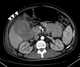

Hemobilia

Haemobilia is a medical condition of bleeding into the biliary tree. Haemobilia occurs when there is a fistula between a vessel of the splanchnic circulation and the intrahepatic or extrahepatic biliary system. [Source: Wikipedia ]